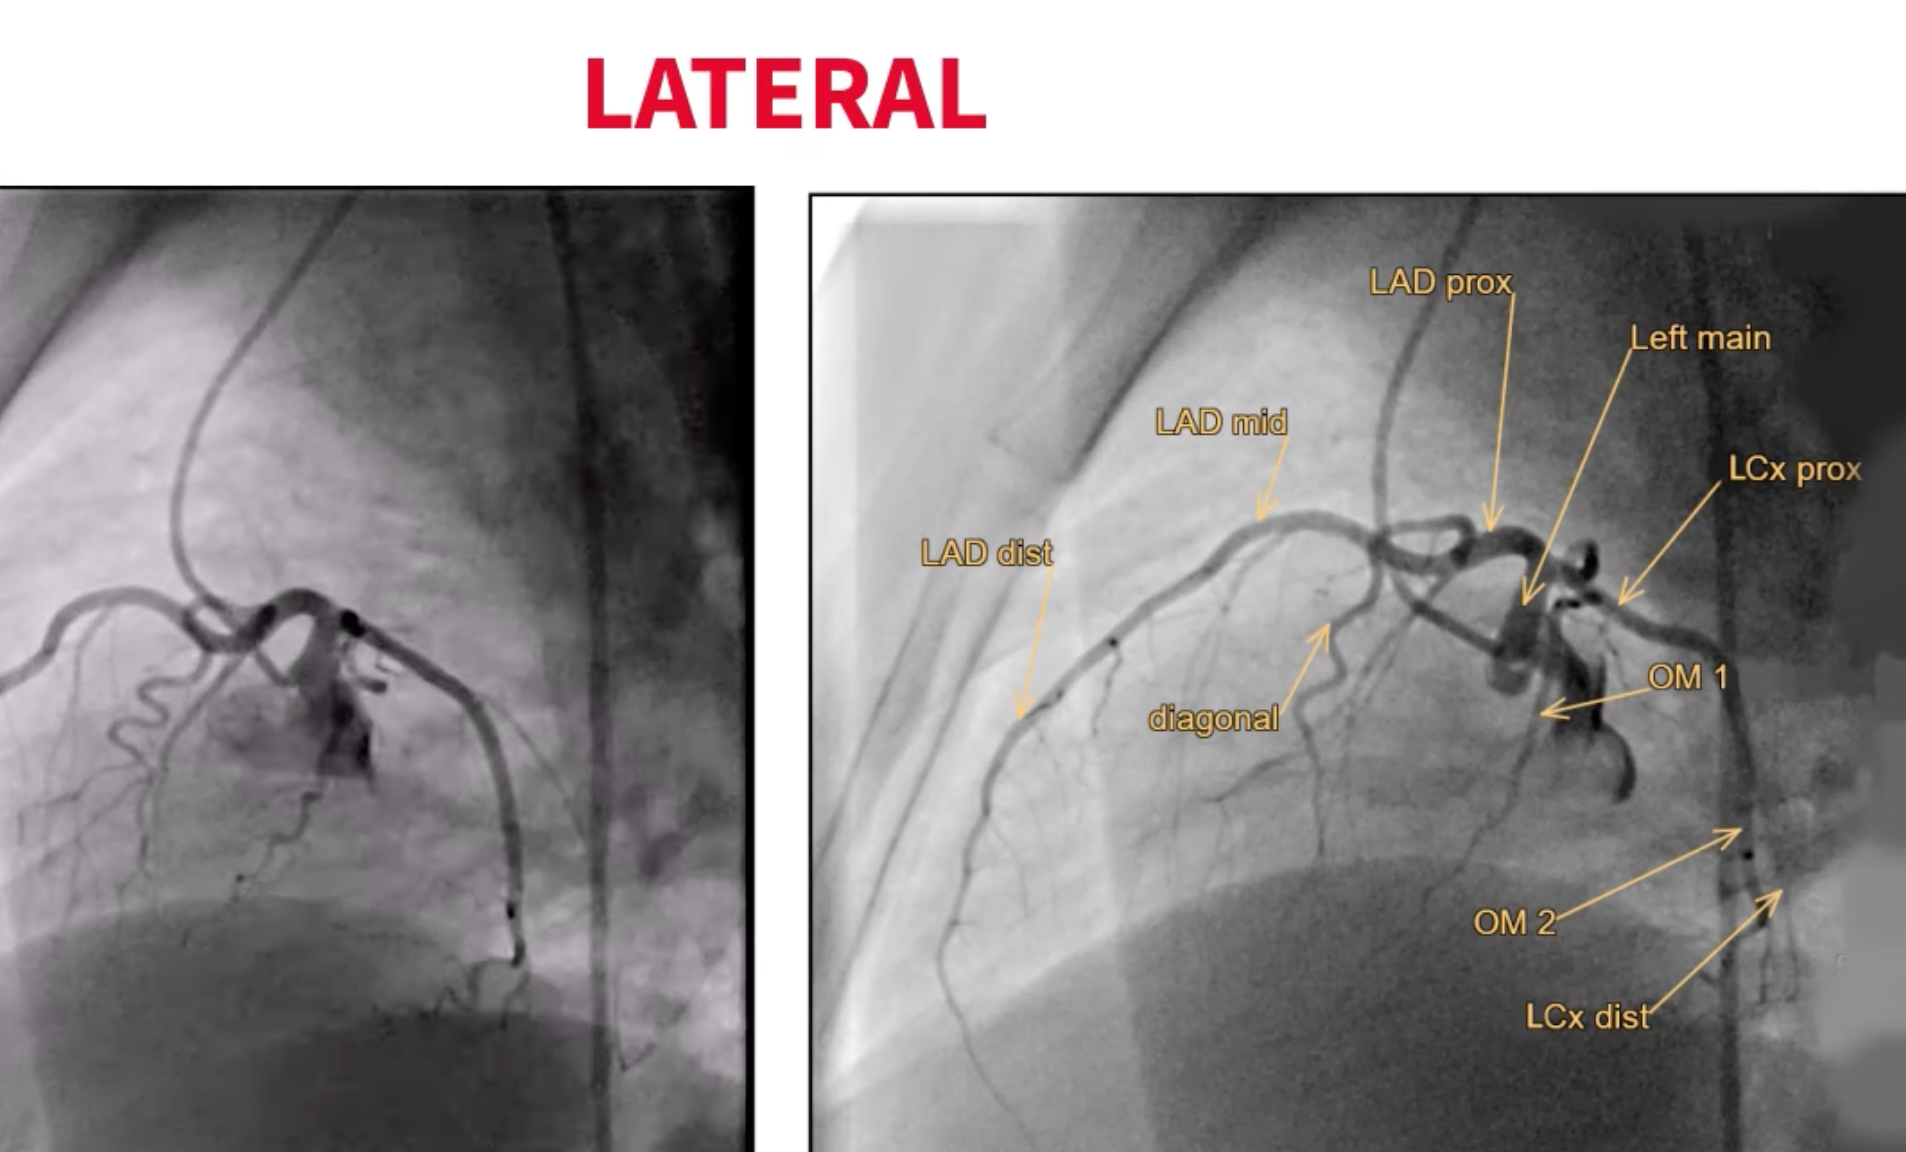

Lateral

- Engaging the left main: